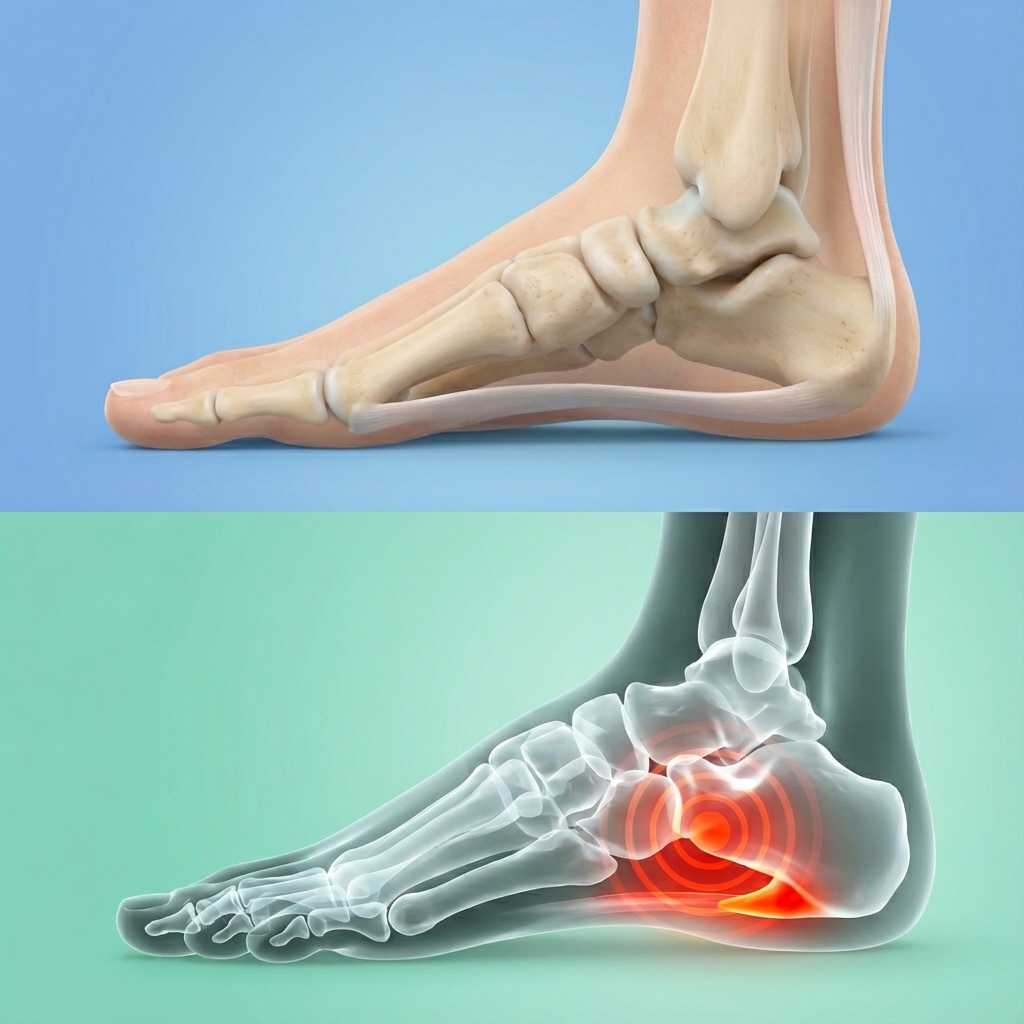

Pod stopą znajduje się mocna płytka ścięgna, czyli powięź podeszwowa.

Przy każdym kroku napina się ona jak lina między piętą a palcami.

Jeśli:

podłoże jest twarde

amortyzacja w bucie jest słaba

sklepienie stopy opada

to przy każdym kroku dochodzi do przeciążenia tego przyczepu ścięgna w pięcie.

Organizm reaguje:

niewielkimi pęknięciami

zapaleniem

i w pewnym momencie ewentualnie wyrostkiem kostnym, znanym jako „ostroga”.

Najgorsze jest to, że

Wystarczy, że nacisk wielokrotnie uderza w niewielki punkt na pięcie.

Dopóki nic się nie zmieni, przy każdym kroku naciskasz na miejsce, które i tak jest już w stanie zapalnym.

Nic dziwnego, że to boli.

Właśnie w tym miejscu stosuje się wkładki.

Ale tylko wtedy, gdy są odpowiednio skonstruowane.